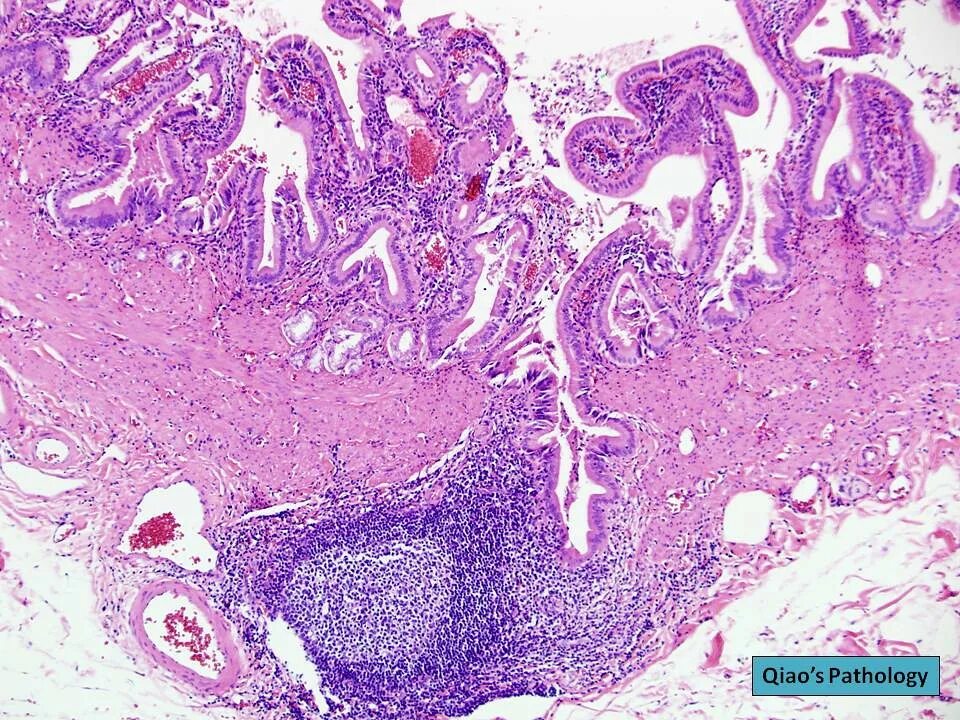

Гистологическая вырезка